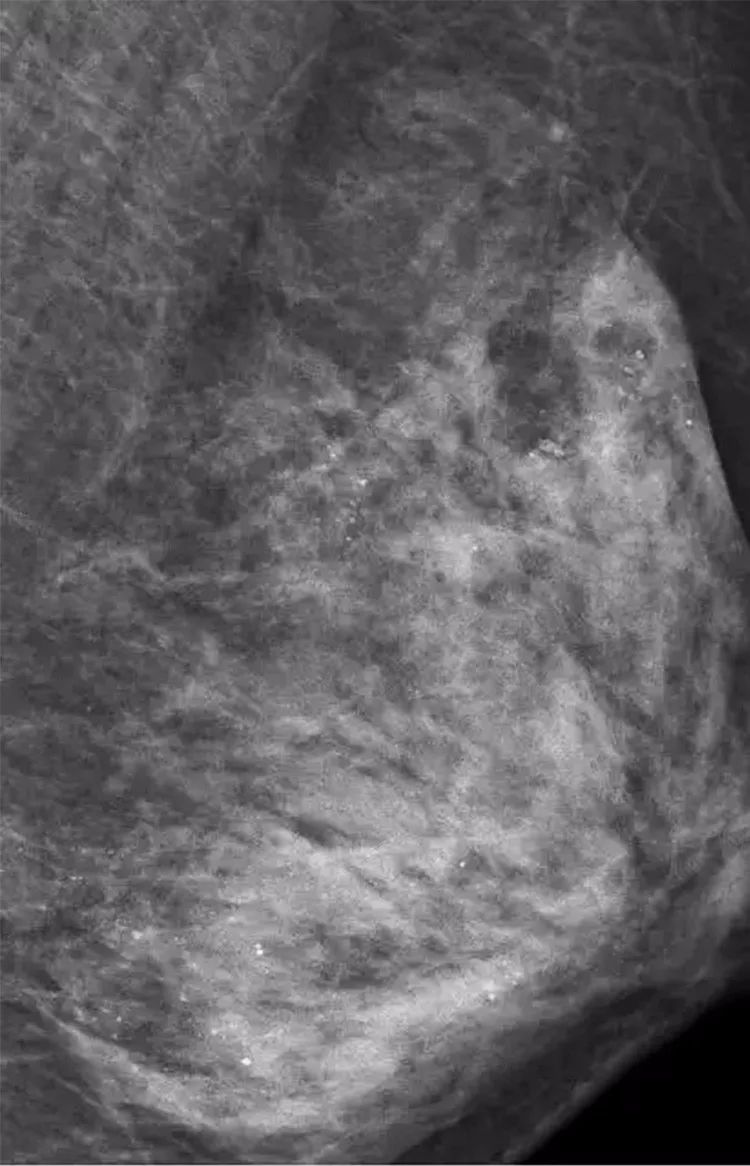

医生在X线检查时,意外地发现,她的左侧乳房乳腺里布满数不清的“沙粒”,全是细小如沙子的钙化灶。

乳腺沙砾样钙化灶是乳癌的信号之一,而当医询问到病史时,她表示,

平时一直在外面做胸部精油推拿按摩。

从而,医生判断:

极有可能是按摩师用力不当损伤了腺叶乳管,导致乳腺出现坏死性细小点状钙化。